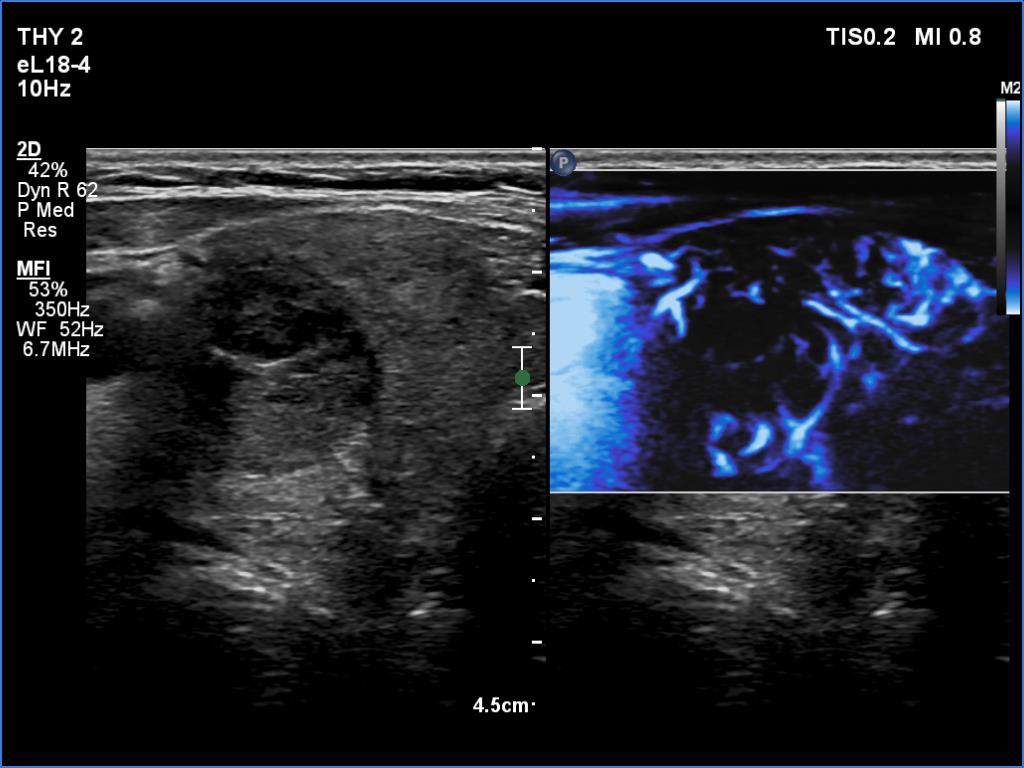

Graves' disease - case 2151

Three years after the first examination (ultrasonographic picture 5)

Right lobe, transverse scan, microflow imaging. The lesion has significantly fewer vessels than the extralesional parenchyma.